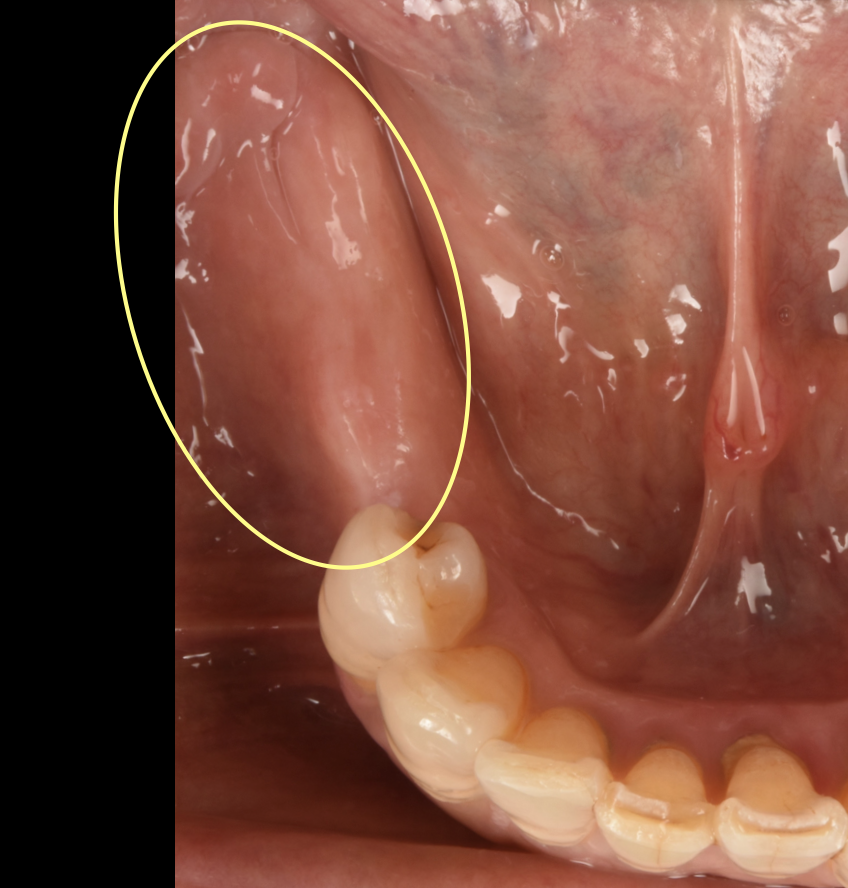

大きな虫歯と根の破折で抜歯適応となった歯を複数本インプラントで再建した症例

初診時。複数本のブリッジがグラついて食べ物が噛めないとのことでご来院されました。レントゲン写真で精査すると、土台に大きな虫歯ができて、一部脱離していることがわかりました。ブリッジを外してみると、そこに…